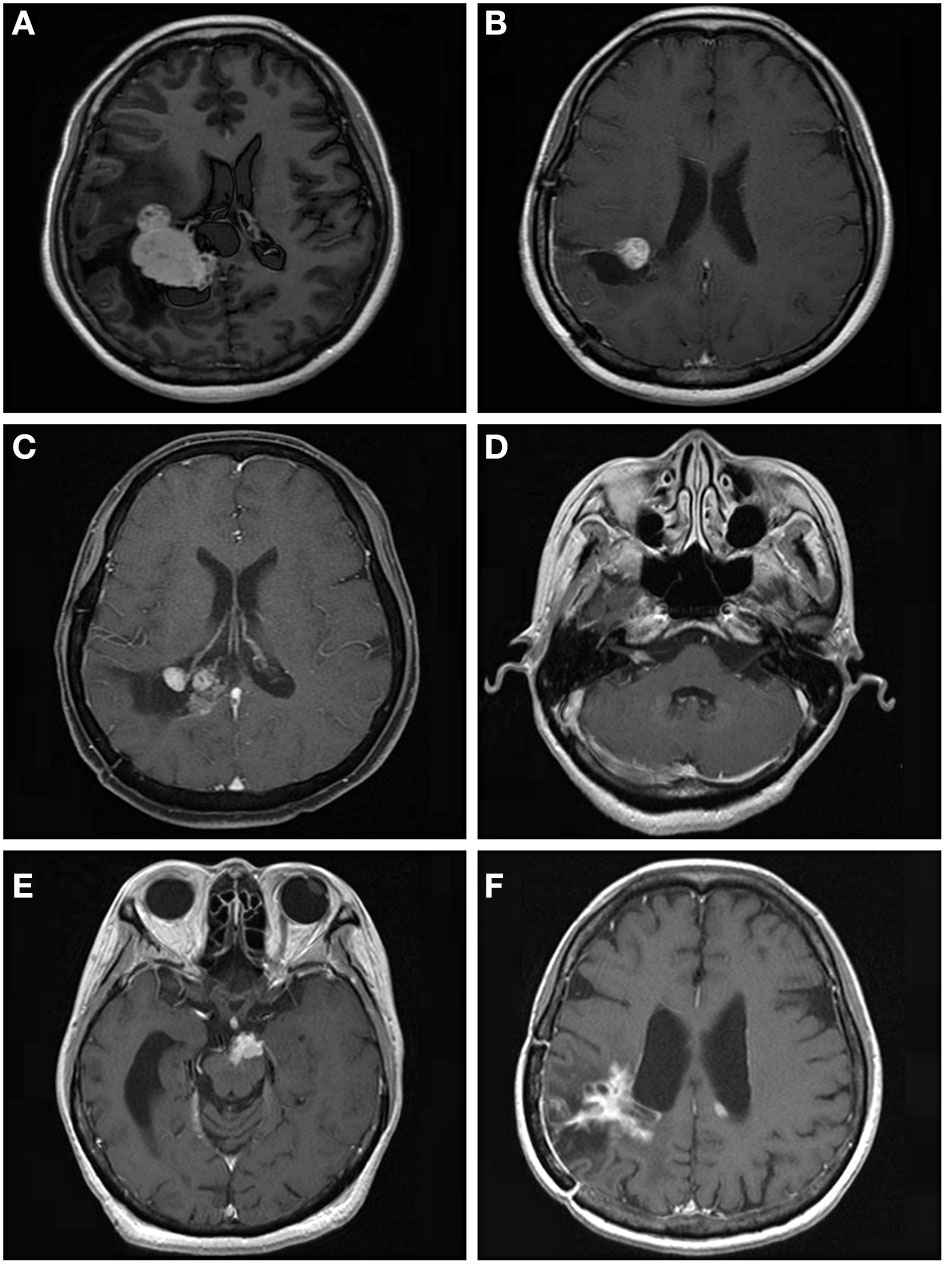

For further treatment of tumor progression, 29 patients underwent repeat GKRS, one patient underwent tomotherapy, seven patients died, and 14 patients underwent surgical resection with or without GKRS. Of the 14 patients, eight patients had malignant transformation with a histological diagnosis of WHO grade II. In addition, one patient with intracranial implantation metastasis 111.7 months after surgical resection was also considered to have malignant transformation (Figure 3). Finally, nine patients presented with malignant transformation. The median time to malignant transformation was 111.7 months (ranging from 35.0 to 177.2 months).

Figure 3

A 53.9-year-old woman with intraventricular World Health Organization (WHO) grade I meningioma received Gamma Knife radiosurgery (GKRS) (margin dose, 13.5 Gy; maximum dose, 30 Gy) as adjuvant treatment for residual tumor after surgical resection. The patient developed local tumor progression and intracranial implantation metastasis at 59.9 and 111.7 months, respectively. (A) contrast-enhanced T1-weighted magnetic resonance imaging (MRI) scans showed an intraventricular tumor. (B) Adjuvant GKRS for residual meningioma after surgical resection. (C) The patient developed local tumor progression at 59.9 months after GKRS. (D–F) The patient developed cerebellopontine angle, brainstem, and intraventricular metastasis at 111.7 months after surgical resection.